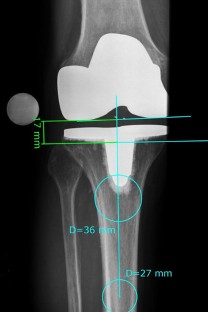

Fig. 2